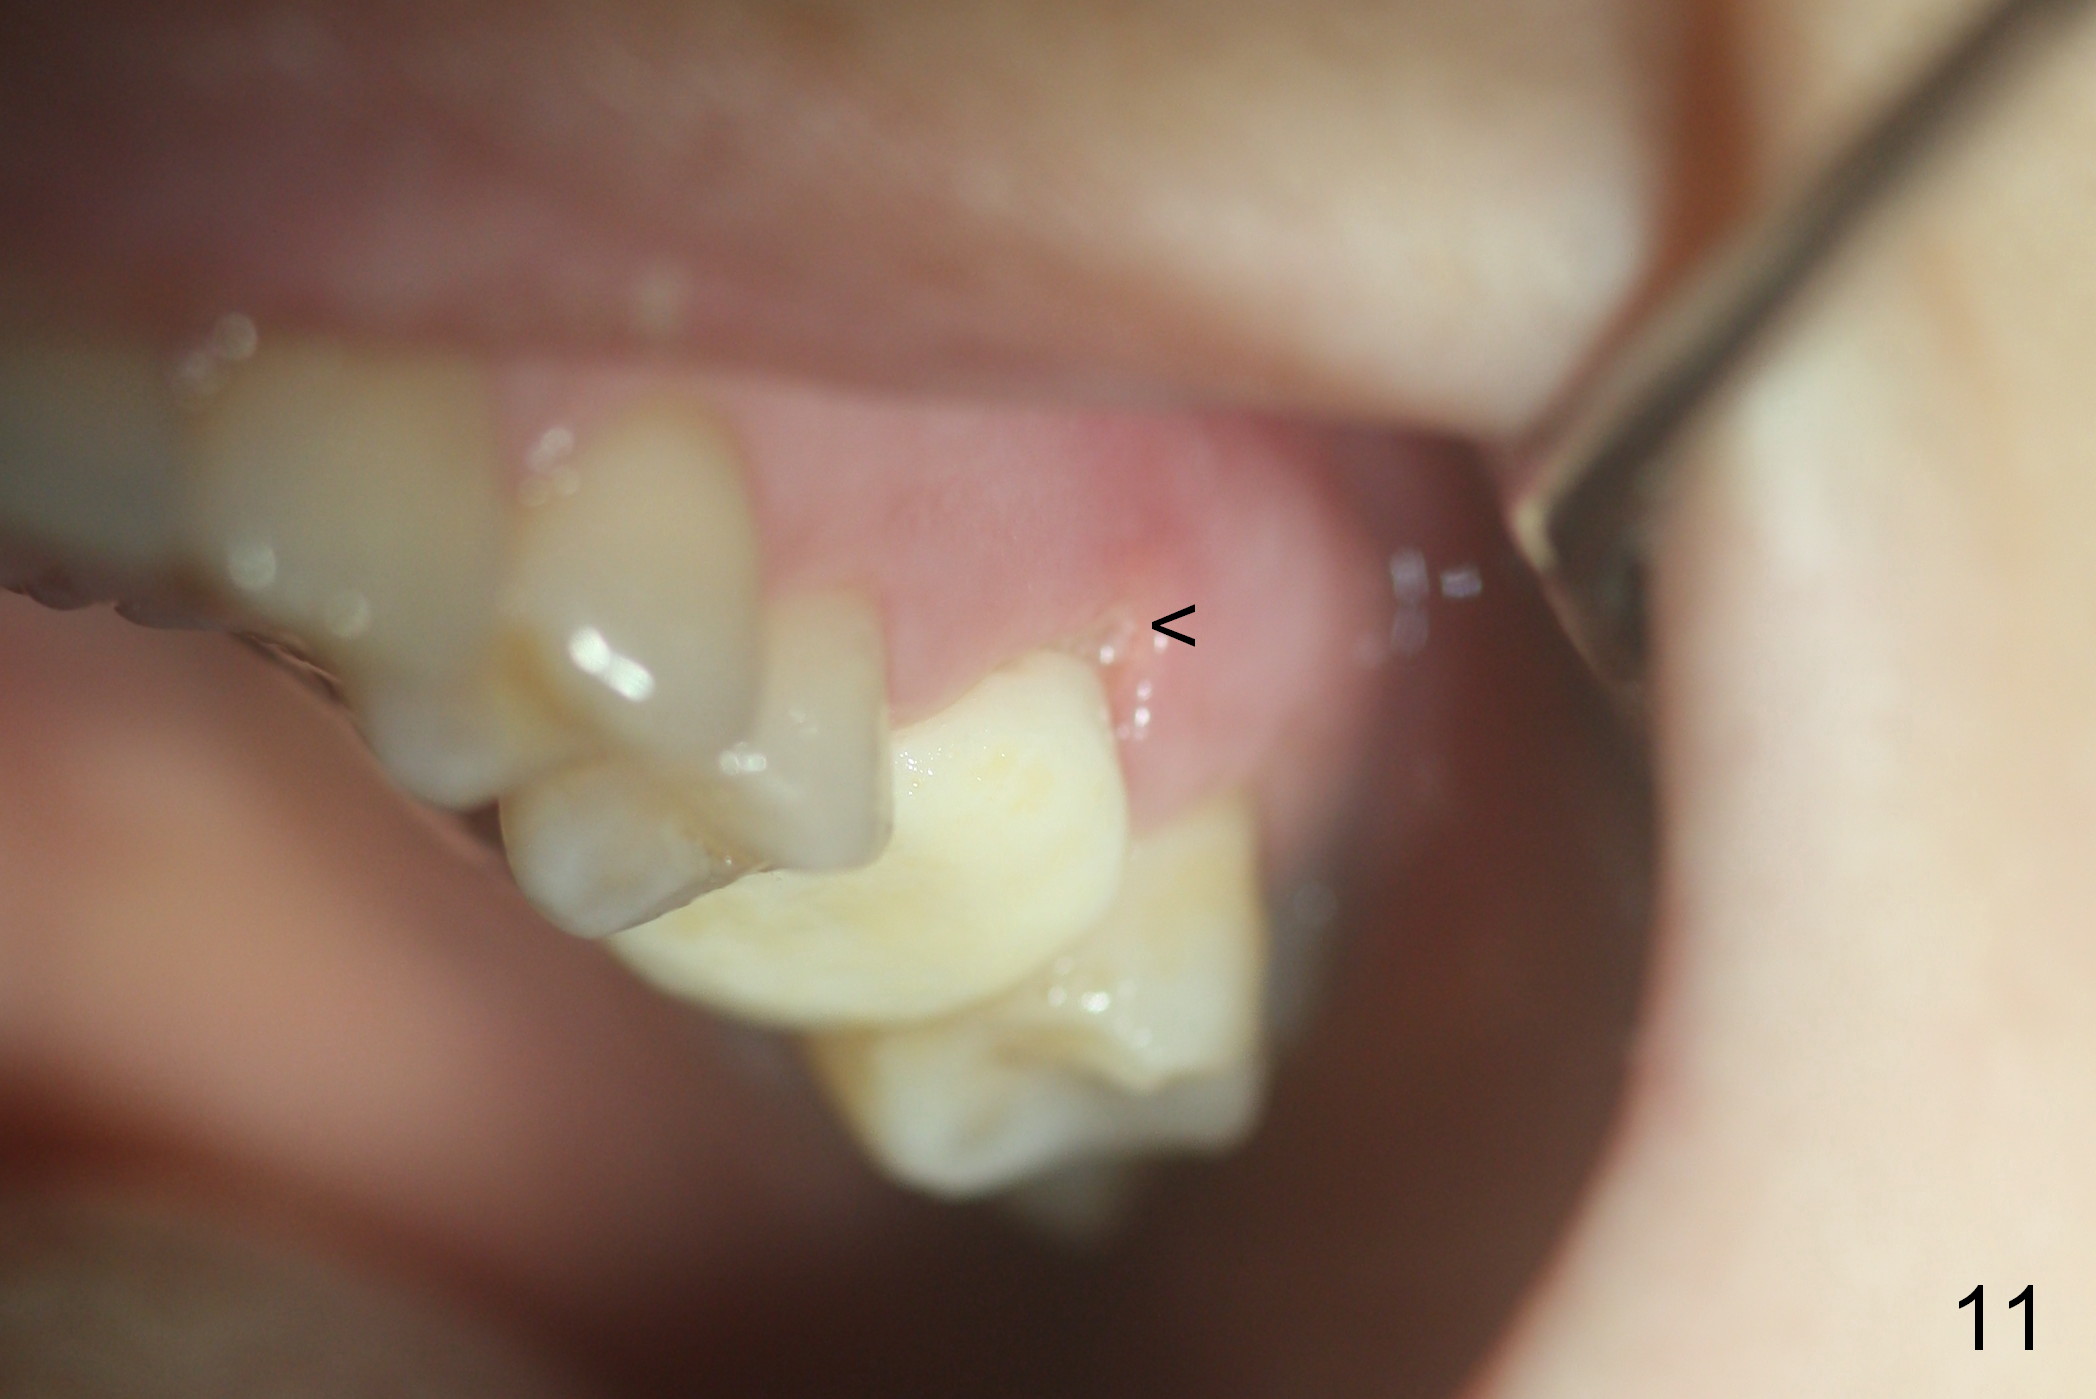

Mild palatal swelling is present around the former fistula 9 days postop (Fig.10 *). No treatment is rendered. There is small buccal gap with exposure of the bone graft (Fig.11 <). Periodontal dressing is applied to prevent further loss of bone graft (Fig.12).